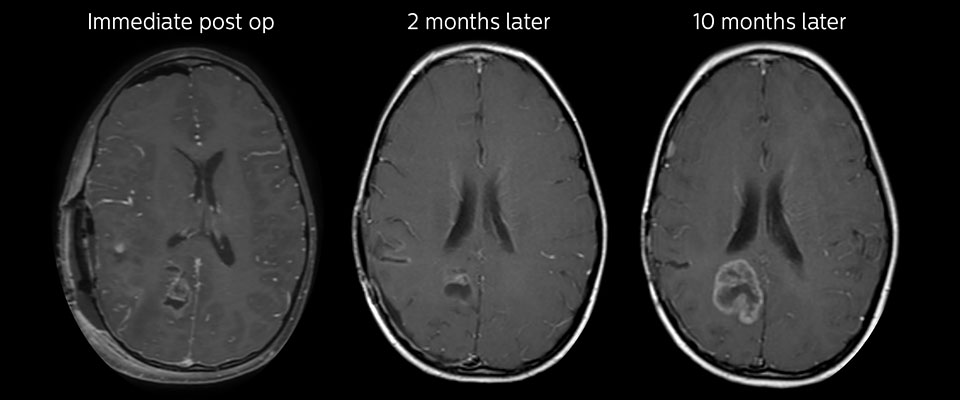

Nachuntersuchung im Laufe der Zeit

In späteren Nachuntersuchungsscans weisen die kontrastverstärkten T1-gewichteten Bilder auf rezidivierendes Tumorwachstum hin. Daher wäre es interessant, den prädiktiven Wert von APT in einer großen Patientengruppe zu untersuchen.